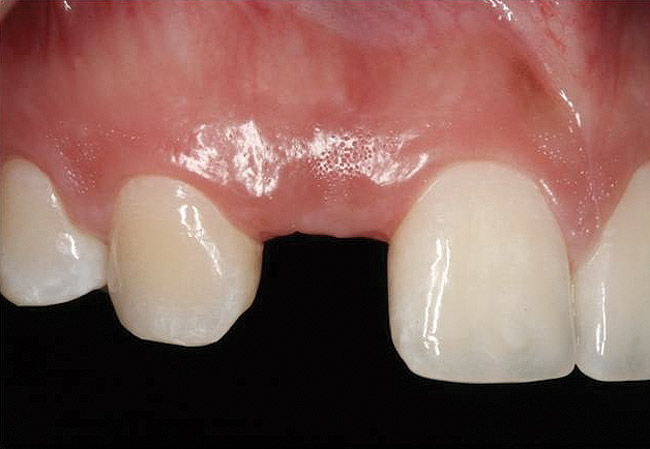

Figure 10 Clinical examination of the bound edentulous space: Measurement of the distal (Fig 10) and mesial (Fig 11) interproximal tissue height using a periodontal probe supplements data obtained from the periapical radiograph. Estimation of the buccal t

Figure 10

Figure 11 Clinical examination of the bound edentulous space: Measurement of the distal (Fig 10) and mesial (Fig 11) interproximal tissue height using a periodontal probe supplements data obtained from the periapical radiograph. Estimation of the buccal t

Figure 11

Figure 12 Clinical examination of the bound edentulous space: Measurement of the distal (Fig 10) and mesial (Fig 11) interproximal tissue height using a periodontal probe supplements data obtained from the periapical radiograph. Estimation of the buccal t

Figure 12